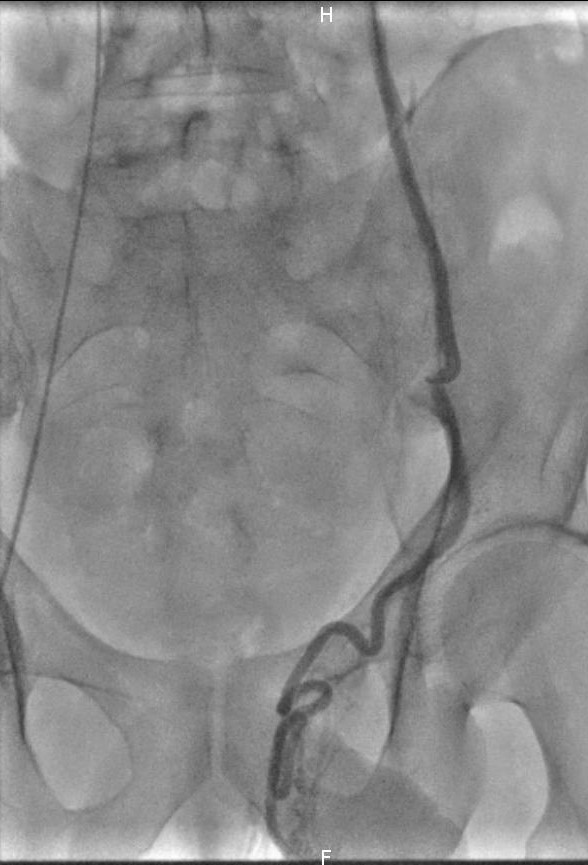

Le radiologue interventionnel réalise une anesthésie locale au niveau du point de ponction à la racine de la cuisse (veine fémorale). Il insère ensuite sous contrôle échographique un cathéter (petit tuyau) dans votre système veineux jusqu’au niveau des veines du rein et du pelvis afin de réaliser une veinographie (cartographie des veines) afin de repérer et cartographier la veine spermatique anormalement refluante, responsable de la varicocèle.

Le radiologue interventionnel positionne ensuite le cathéter à l’endroit souhaité dans la veine spermatique puis procède à l’injection de l’agent embolisant (colle, coils). Il pourra